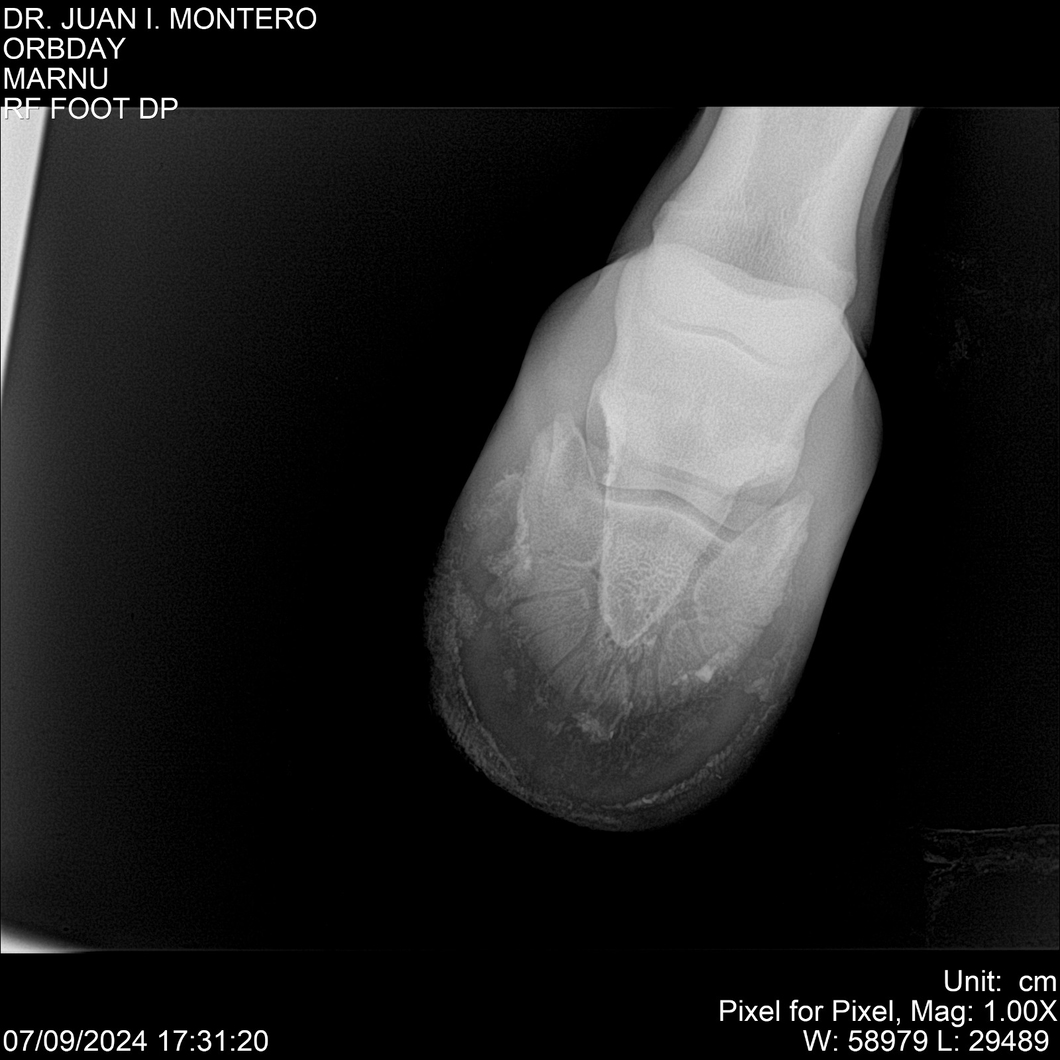

• Empresa: Abelenda N. R., Walter Hugo